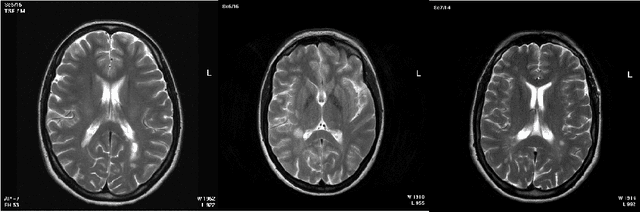

Abstract:Magnetic resonance images (MRI) play an important role in supporting and substituting clinical information in the diagnosis of multiple sclerosis (MS) disease by presenting lesion in brain MR images. In this paper, an algorithm for MS lesion segmentation from Brain MR Images has been presented. We revisit the modification of properties of fuzzy -c means algorithms and the canny edge detection. By changing and reformed fuzzy c-means clustering algorithms, and applying canny contraction principle, a relationship between MS lesions and edge detection is established. For the special case of FCM, we derive a sufficient condition and clustering parameters, allowing identification of them as (local) minima of the objective function.